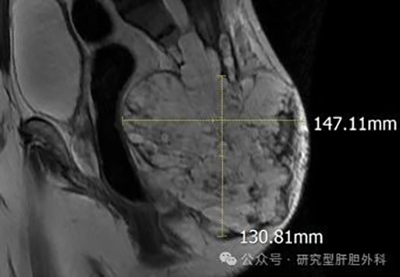

核磁报告:骶尾部骨质破坏消失,肿瘤上下范围约17cm,深度14cm,向两侧累积臀部肌肉,上界至骶2水平,向前至直肠后壁。髂骨、双侧股骨头、右股骨干、腰4、腰5椎体多发转移。同时患者考虑合并肝、肺等多处转移。

术前核磁图像